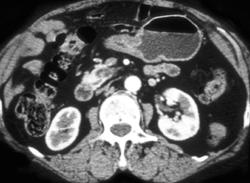

Normal Stomach With Simulated Tumor Due to Collapse